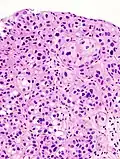

Histopathology of transitional carcinoma of the urinary bladder. Transurethral biopsy. Hematoxylin and eosin stain.

Transitional refers to the histological subtype of the cancerous cells as seen under a microscope.